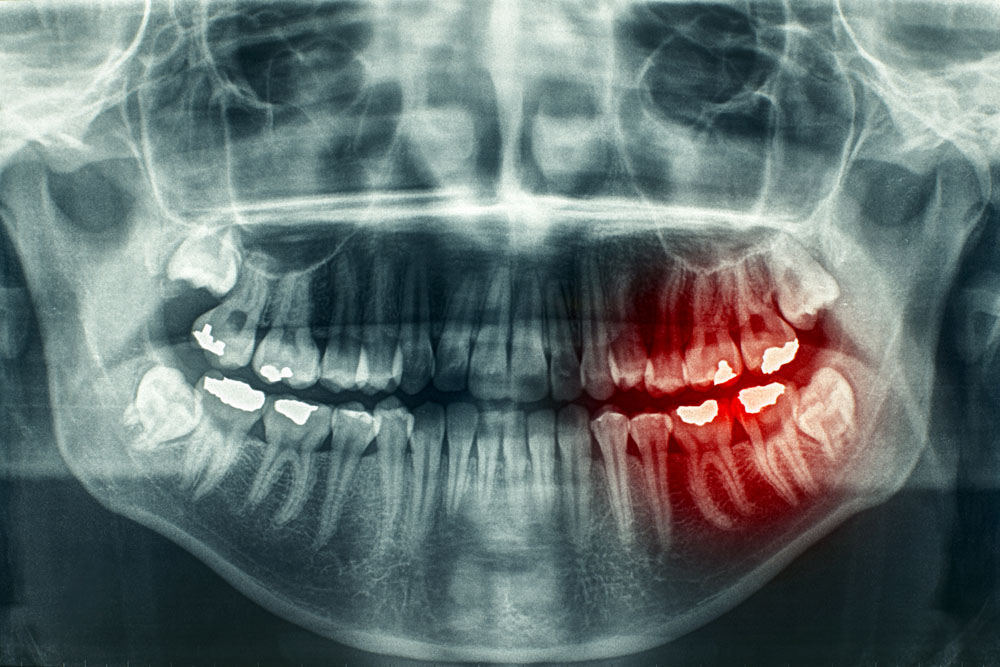

那么,大家有过牙痛的经历么,牙痛不算病,痛起来要人命,每当牙痛难忍时,怎么办呀。

医生告诉你:“要杀神经。”

患者:“好哇,赶紧杀死神经吧,折磨我好多天了。嘻嘻。”

牙痛是请杀神经

就如:牙痛,杀神经。